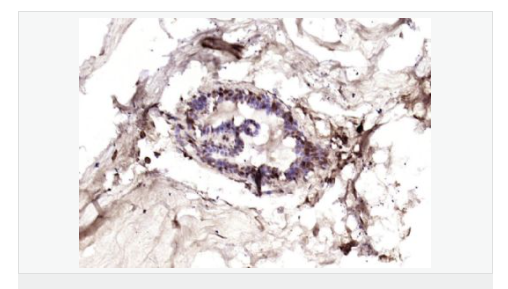

產(chǎn)品應用ELISA=1:5000-10000 IHC-P=1:100-500 IHC-F=1:100-500 IF=1:100-500 (石蠟切片需做抗原修復)

細胞定位細胞核 細胞漿 細胞膜